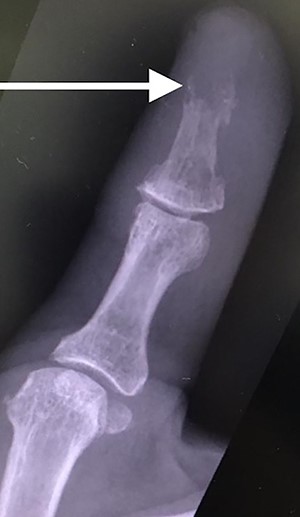

The patient was then reviewed 6 weeks after her initial presentation, following the results of the sarcoma MDT, which confirmed a benign tumour. At this point, the patient reported some tenderness around the surgical incision, but that her symptoms were improving. It was thought that she had no signs of ongoing infection in the thumb. The outcome was for monitoring of her symptoms with no indication for surgical excision. She had a follow-up X-ray in 6 weeks’ time that showed resolution of the lytic lesion (Figs 6 and 7).

Lateral follow-up radiograph of right thumb 6 weeks post-admission showing resolution of lytic lesion.